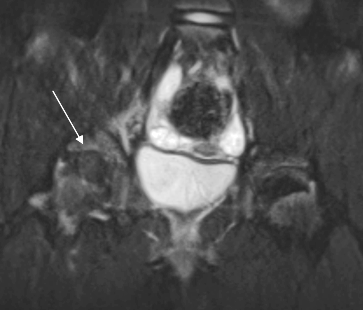

La ragazza � stata dimessa in corso di trattamento antibiotico, con consiglio di evitare il carico dell'articolazione. Il follow-up ha dimostrato un ritorno alla normalit� degli indici infiammatori e una progressiva ripresa della funzionalit� motoria. Il controllo dell'articolazione tramite RM a quattro mesi ha dimostrato un reperto normale (Figura 2)

Figura 2. RM, Coronale FSE T2 Fat-sat: Controllo a 4 mesi dopo terapia. Scomparsa dell'edema intraspongioso e del versamento intra-articolare. Risoluzione della raccolta muscolare (freccia).